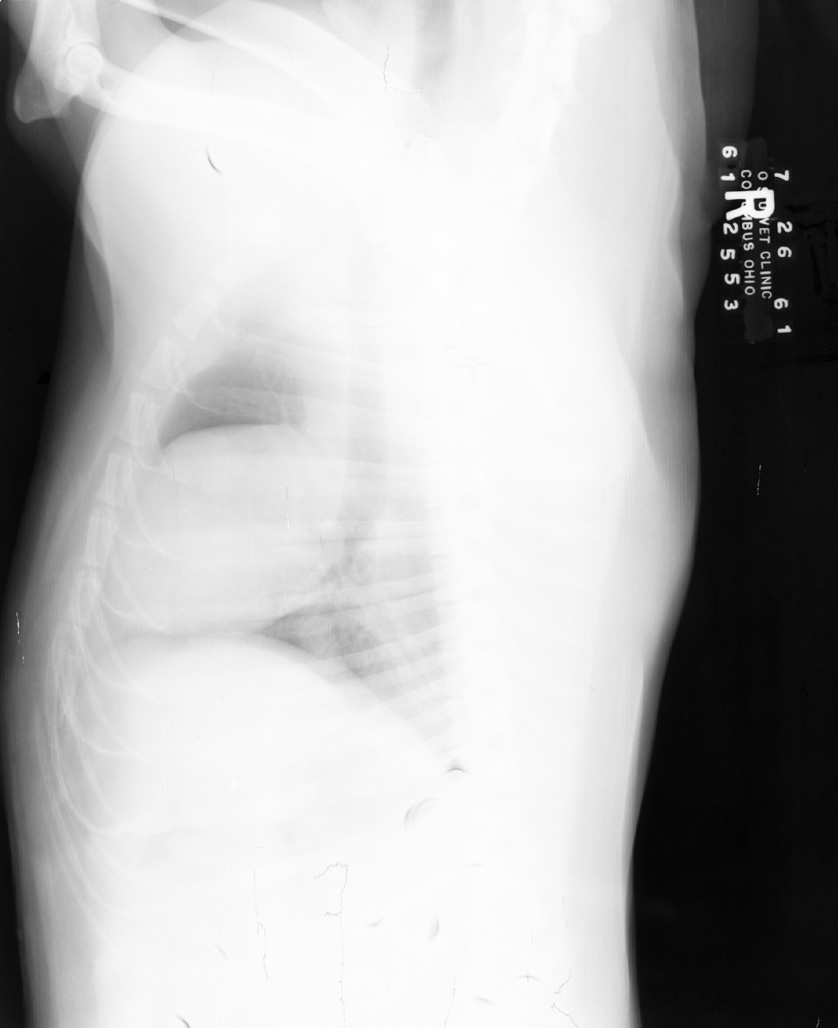

Underexposure, Rough Film Handling

Folding of film results in crescent-shaped artifacts which may be white or black, depending on how roughly the film is mishandled. White marks are pre-exposure, and black marks are post-exposure.